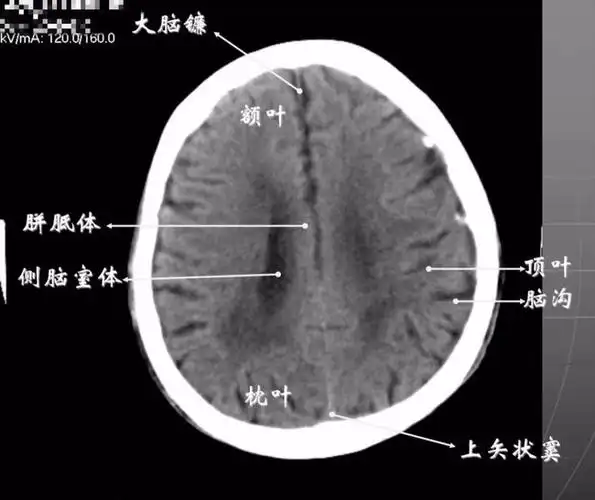

读懂头颅ct并不难,教你成为读片小能手